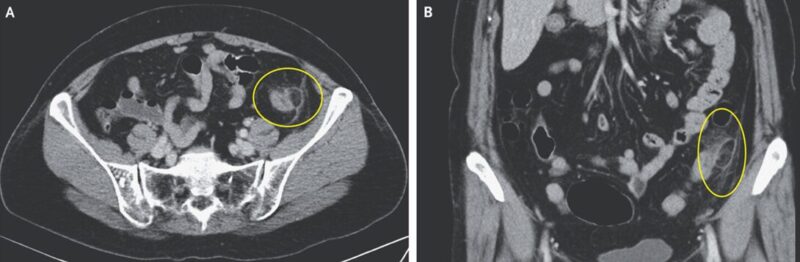

40歳男性。嘔吐と下痢で救急外来を受診した。 特記すべき既往もなく、特段変わった治療歴もなかった。 バイタルはHR 132である以外は正常だった。 身体所見では…